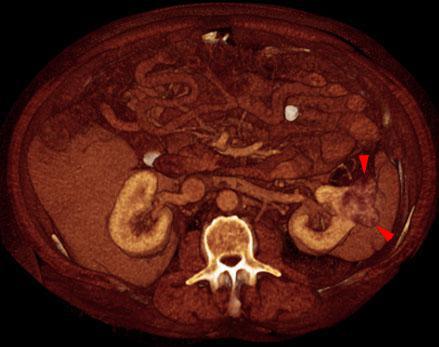

Hipernefroma 2

VR seccional. Visión axial caudal. TC contrastado en fase venosa que muestra en el riñón izquierdo una tumoración sólida y polilobulada (puntas de flecha), con captación del contraste